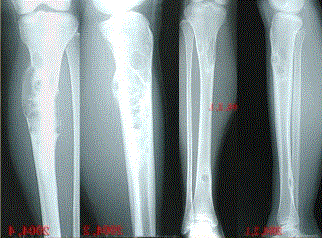

问题 患者女,20岁,右小腿疼痛1周。行双小腿正侧位CR,并行双小腿CT及MR扫描,见下图。 此病变最可能的诊断是

选项 A.骨囊肿 B.动脉瘤样骨囊肿 C.骨纤维异常增生症 D.骨巨细胞瘤 E.非骨化性纤维瘤

答案 C